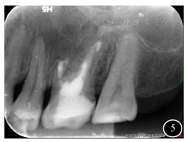

术后即刻根尖片示:26的MB、MB2、DB、P根管倒充填致密,原根尖低密度影区见高密度充填物影(图5)。

阿替卡因局部浸润麻醉,于25至27切开翻瓣,口腔手术显微镜下见26根尖骨质缺损区,刮除病变区肉芽组织,切除26腭根、近颊根、远颊根各3 mm,亚甲基蓝染色,未见明显裂纹。显微镜下见MB2内无根充物,探及根管钙化。超声工作尖行MB、MB2、DB、P根管根尖倒预备各3 mm,iRoot BP Plus ®分层倒充填,修整根面,庆大霉素浸泡术区,放置Bio-Oss ®骨粉,覆盖Bio-Gide ®胶原膜。复位,缝合(图4)。